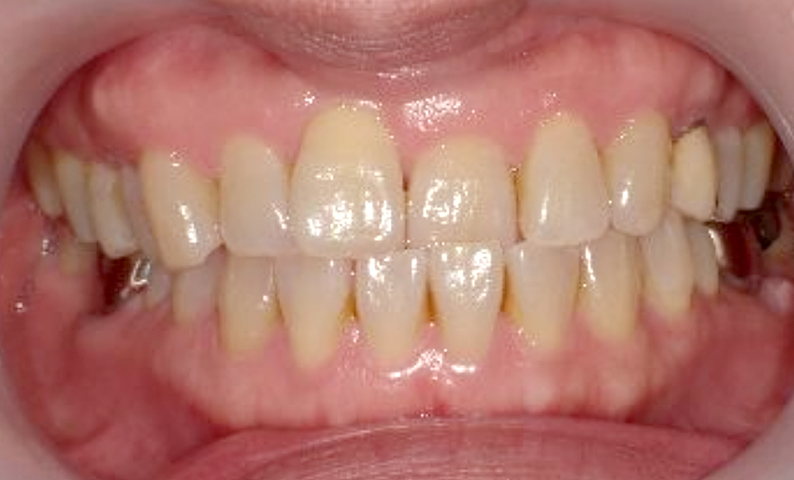

症例_003 下顎だけの部分矯正

治療期間:10ヶ月金額:24万円+税女性前歯のガタガタ下の前歯だけ上顎は補綴治療中

| Before | After |